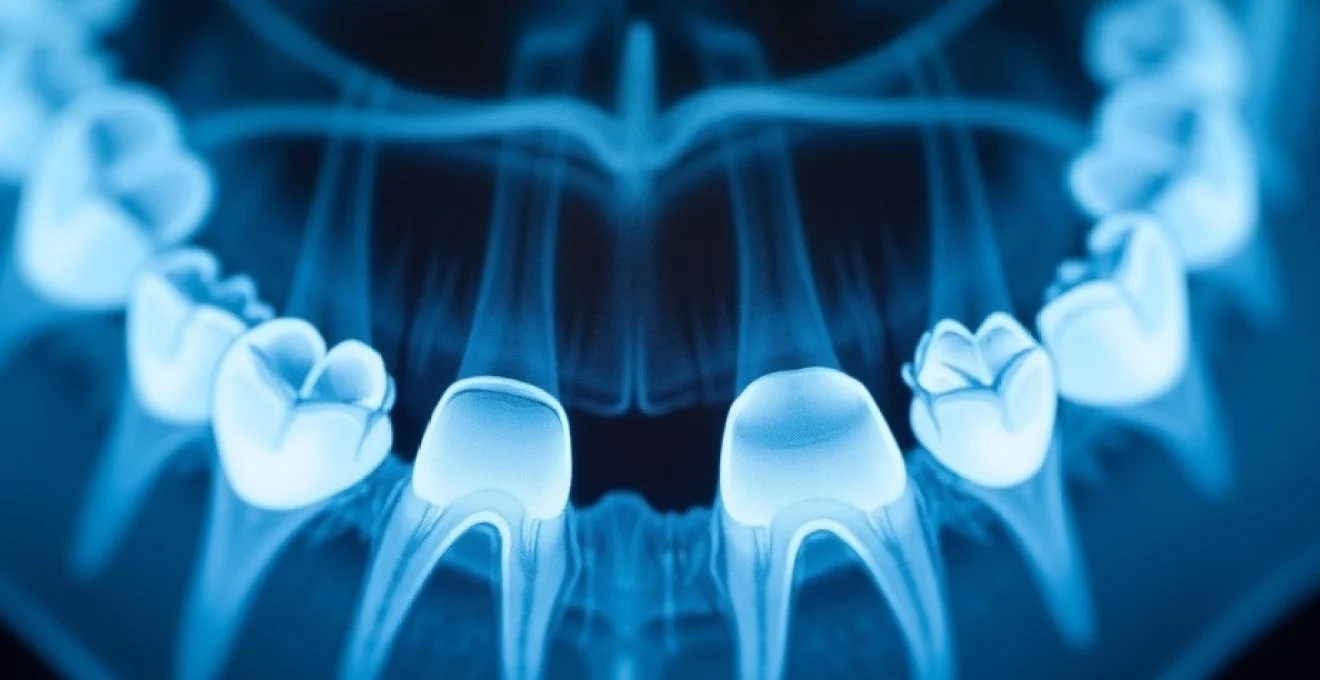

La radiologie dentaire numérique repose sur l’utilisation de capteurs électroniques qui convertissent les rayons X en images numériques. Cette technologie offre de nombreux avantages par rapport aux techniques traditionnelles de radiographie sur film. Les images obtenues sont de meilleure qualité, avec un contraste et une netteté supérieurs, permettant une analyse plus fine des structures dentaires et osseuses.

Les systèmes de radiographie intra-orale numériques ont considérablement amélioré la qualité et la précision des images dentaires individuelles. Ces systèmes utilisent des capteurs numériques placés directement dans la bouche du patient pour capturer des images détaillées des dents et des structures environnantes.

Les caries interproximales, qui se développent entre les dents, sont souvent difficiles à détecter lors d’un examen visuel. Les radiographies intra-orales, en particulier les bitewings , sont extrêmement efficaces pour identifier ces lésions à un stade précoce. De même, les caries radiculaires, qui affectent la racine de la dent, peuvent être détectées grâce à des radiographies périapicales avant qu’elles ne causent des dommages importants.